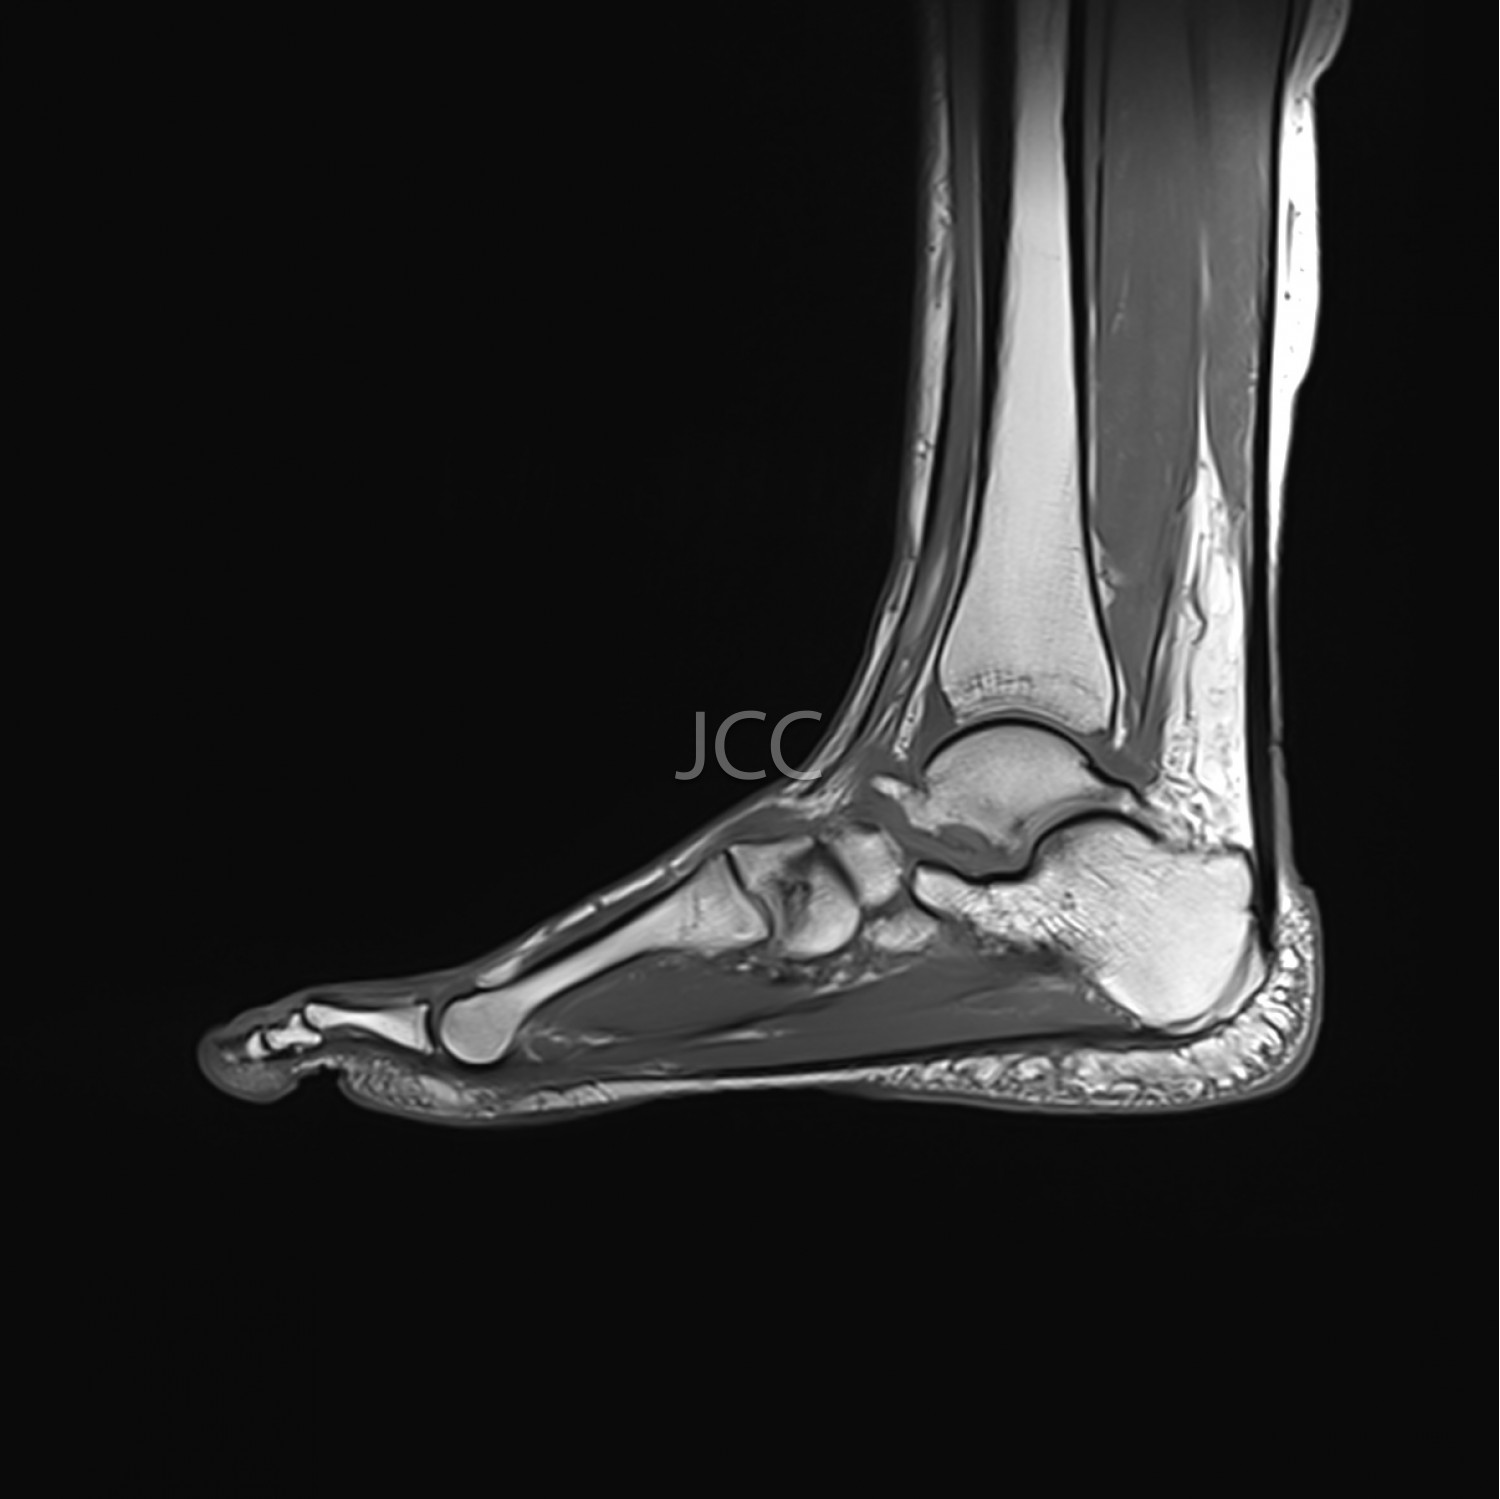

Ressonância Magnética de Alto Campo - RM Osteo-Articular

A Ressonância Magnética de Alto Campo é uma técnica de imagem que não utiliza radiação baseando-se num campo magnético e ondas de radiofrequência para estudar detalhadamente os órgãos do corpo humano.

Atualmente, com os equipamentos mais modernos de 1.5 e 3 TESLA é possível não só estudar cérebro, coluna e articulações constituindo, também, a técnica de eleição para avaliação vascular, coração, fígado e pâncreas.